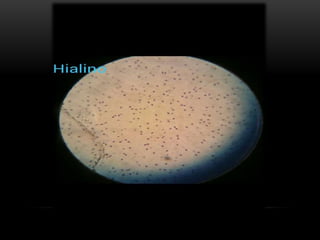

El documento presenta un estudio de histología dividido en 6 capítulos. Cada capítulo se enfoca en un tipo diferente de tejido: el capítulo 1 en tejido epitelial, el capítulo 2 en tejido conectivo general, el capítulo 3 en tejido conectivo cartilaginoso, el capítulo 4 en tejido conectivo óseo, el capítulo 5 en tejido muscular y el capítulo 6 en tejido nervioso y el sistema nervioso.